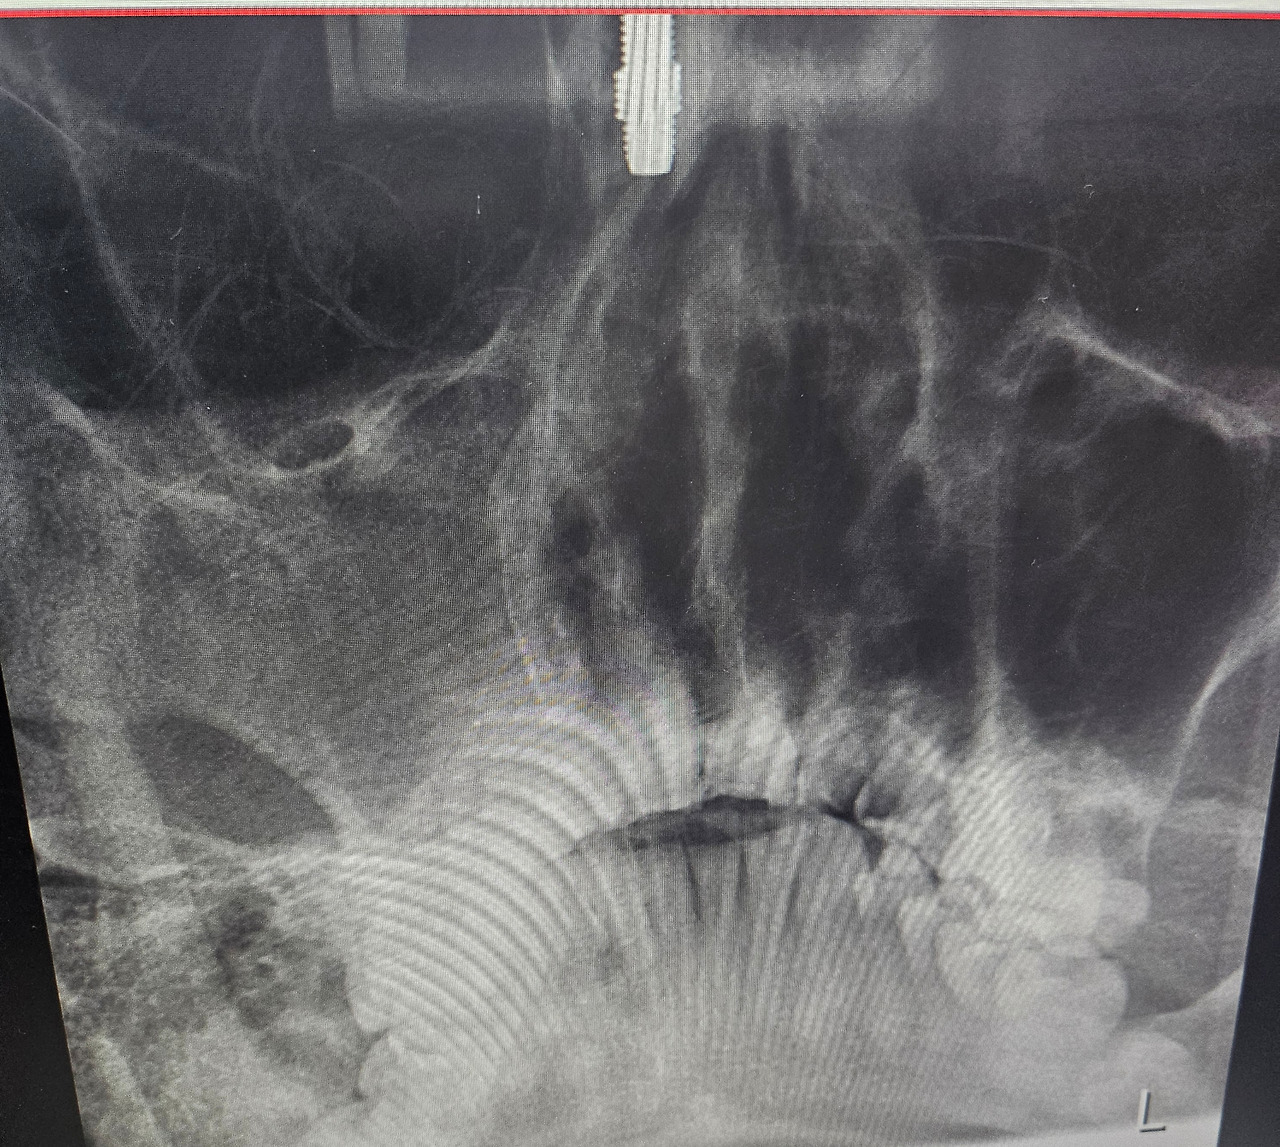

새해가 시작되고 나의 방학도 시작되었다. 1월 말에 개학이 있고 2주나 더 학교를 나가야 했지만 지금 이 순간부터는 온전히 가족과 함께 시간을 보낼 수 있게 된 것이다. 딱 3주간의 시간이 허락되어 무엇을 해볼까 싶었다가도 제한이 많은 시기라 크게 하지는 못했다. 여기서 제한은 여러 가지가 있겠으나 가장 큰 것이 날씨였다. 추운 날씨는 야외활동에 제한을 두었고 우리 몸에도 불편을 주었다. 아기와 엄마는 계속 감기에 걸려 있었고 나 역시 감기가 오래갔다. 내가 제일 먼저 괜찮아졌지만 큰 문제가 발견되었다. 제일 힘겨워하던 아내는 몸이 좋아지는 속도가 빨라졌고 아기는 한 달째 약을 먹고 있었다. 즉, 아기와 내가 제일 문제였다. 우선 나는 이비인후과에서 검사를 했는데 오른쪽 부비동(광대뼈 안쪽)에 농이 가득 차 있었다. 예전부터 알고는 있었지만 계속 뒀다간 더 심해질 수 있어 수술울 권유하셨다. 2주가량 고민을 하다 수술을 하기로 결정하고 지금 기다리고 있는 상태고 아기는 감기가 나았다 싶었으나 더 심해져 항생제를 계속 먹어 댔다. 가급적 약을 덜 먹이고 키우고 싶은 것이 부모의 마음이건만 쉽지가 않다. 그렇게 꼬박 한 달간 약을 먹고서야 괜찮아졌다.

부비동염을 이제는 그냥 둘 수 없다.